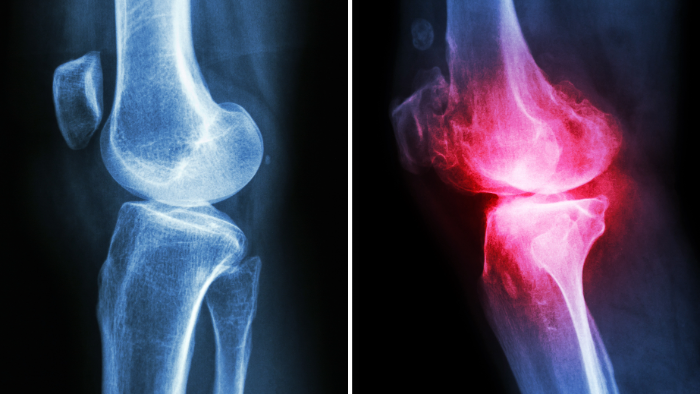

Osteoarthritis: The “Wear-and-Tear” Model

normal knee joint x-ray in comparison to knee joint with osteoarthritis

Osteoarthritis (OA) is by far the most common form of arthritis, especially in older adults. (14) It affects an estimated 33 million Americans, and that number is expected to significantly rise as the population ages. (17) You might hear people call it “degenerative joint disease”, and that’s a pretty good description of what it is, a general degeneration of the joint over time.

In fact, many doctors may tell you your joint pain is just “wear and tear” and comes with age. But that phrase can be a bit misleading. It makes OA sound like a passive, inevitable part of aging, when in reality, it’s a dynamic and degenerative process that affects more than just cartilage, and isn’t always a normal part of aging.

5. Reduced Joint Space

On X-rays, OA often shows up as narrowing of the joint space, a sign that the cartilage is essentially gone. (23) Less space means more stiffness and less freedom to move.